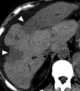

Confluent fibrosis

Retroperitoneal fibrosis or Ormond's disease is a disease featuring the proliferation of fibrous tissue in the retroperitoneum, the compartment of the body containing the kidneys, aorta, renal tract, and various other structures. It may present with lower back pain, kidney failure, hypertension, deep vein thrombosis, and other obstructive symptoms. [Source: Wikipedia ]